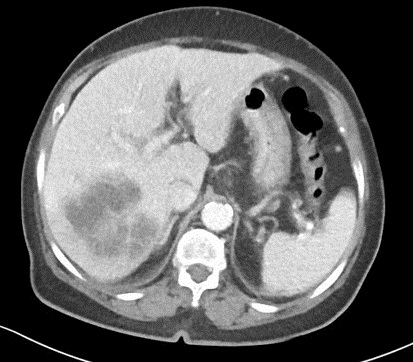

Image radiologique TDM d'une abces

amibien du foie droit avec aspect lesionnel est un masse

hypodensite a paroi epaise attenue et zone de

oedemateuse hypodense peripherique

|

Image en cible

d'une abces du foie droit . CoupeTDM axiale 90

seconde apres injection de contrast intraveineuse .

Aspect lesionnel est un contour hyperdense et un

centre hypodense pseudokystique " double target sign

" |